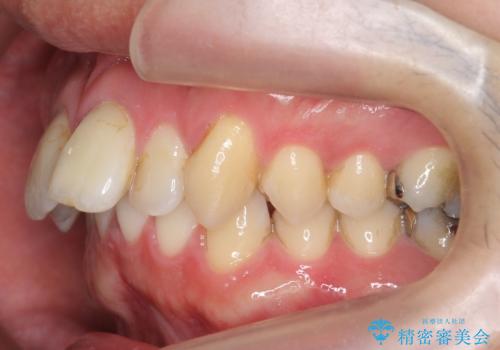

出っ歯を部分矯正で目立たなくする セラミック治療も

- 前歯の突出を主訴に来院。

全体矯正を行うとなると健康な歯を4本抜歯することになるため、歯は抜かず上だけの部分矯正で最小限で前歯を整えることにしました。

左上の1番目の前歯は神経を取ってある歯でした。今後変色もすすんでいくため、治療のやり直しを行いセラミックでかぶせました。

- 部分矯正25万円 左上12(ジルコニアクラウンスペシャル13万円x2、ファイバーコア2万円x2、精密根管治療(左上1:再治療9万円、左上2:初回治療6万円)費用は治療当時の料金となります

左上の2番目の前歯は虫歯治療を行い、神経治療まで行っています。